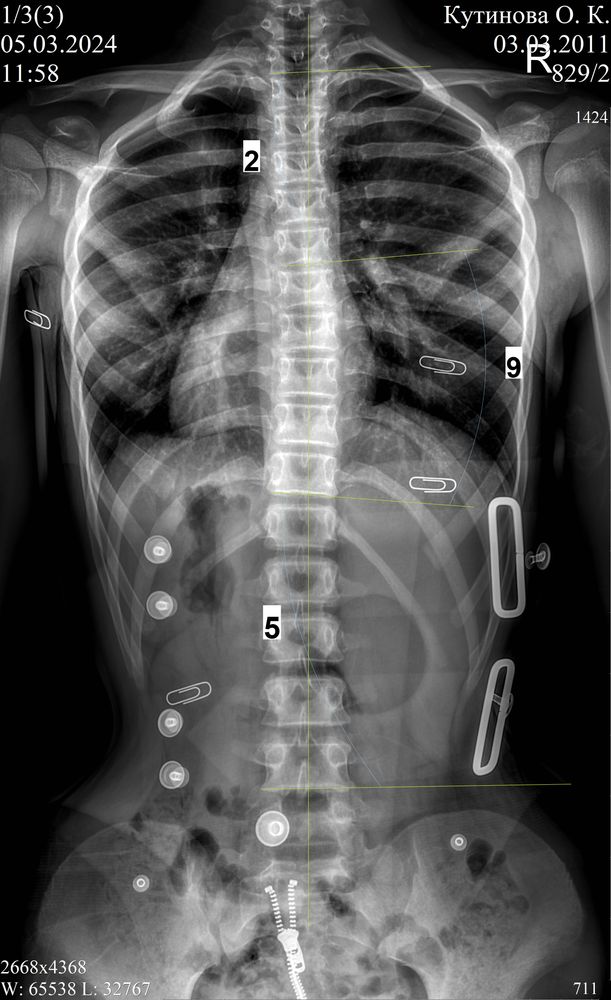

Дополнение от весны 2024 года.

Прошло 6 лет в корсете, дочке 13 лет, режим ношения - ночной сон, днём не носит, спец гимнастику не делает, занимается только обычной физ активностью, пару раз в бассейн, пару раз на танцы, прогулки с собакой.

Фото 2 - в нашем пятом корсете

Апдейт от декабря 2024:

Фото без корсета перед выдачей прошлого корсета ( декабрь 2023), и фото без корсета перед заказом нового ( декабрь 2024). Выросла, 177 см,поэтому опять замена (

В декабре 2024 (6,5 лет в корсете, взраст 13 лет 9 мес) нам сказали что делать новый все таки не будут, градусы маленькие, вдруг гиперкоррекция случится) очень было тревожно, но корсет сняли, через три месяца рентген-осмотр 25.02.2025 - пока все ок, еще три месяца гуляем без корсета. Будем делать рентген каждые три месяца, так сейчас самый опасный момент - М нет, рост идет, за три месяца добавила 1 см, итого 177,5 см, через 5 дней 14 лет.